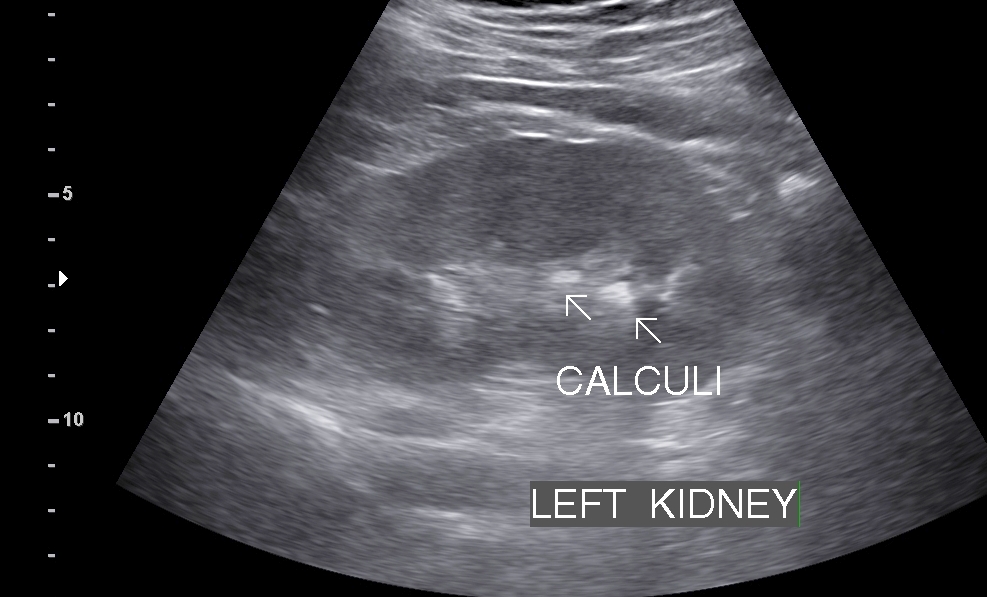

• Sonography: Sonography can show presence of renal calculi, their number, size, location with signs of obstruction.

• Renal Calculi: